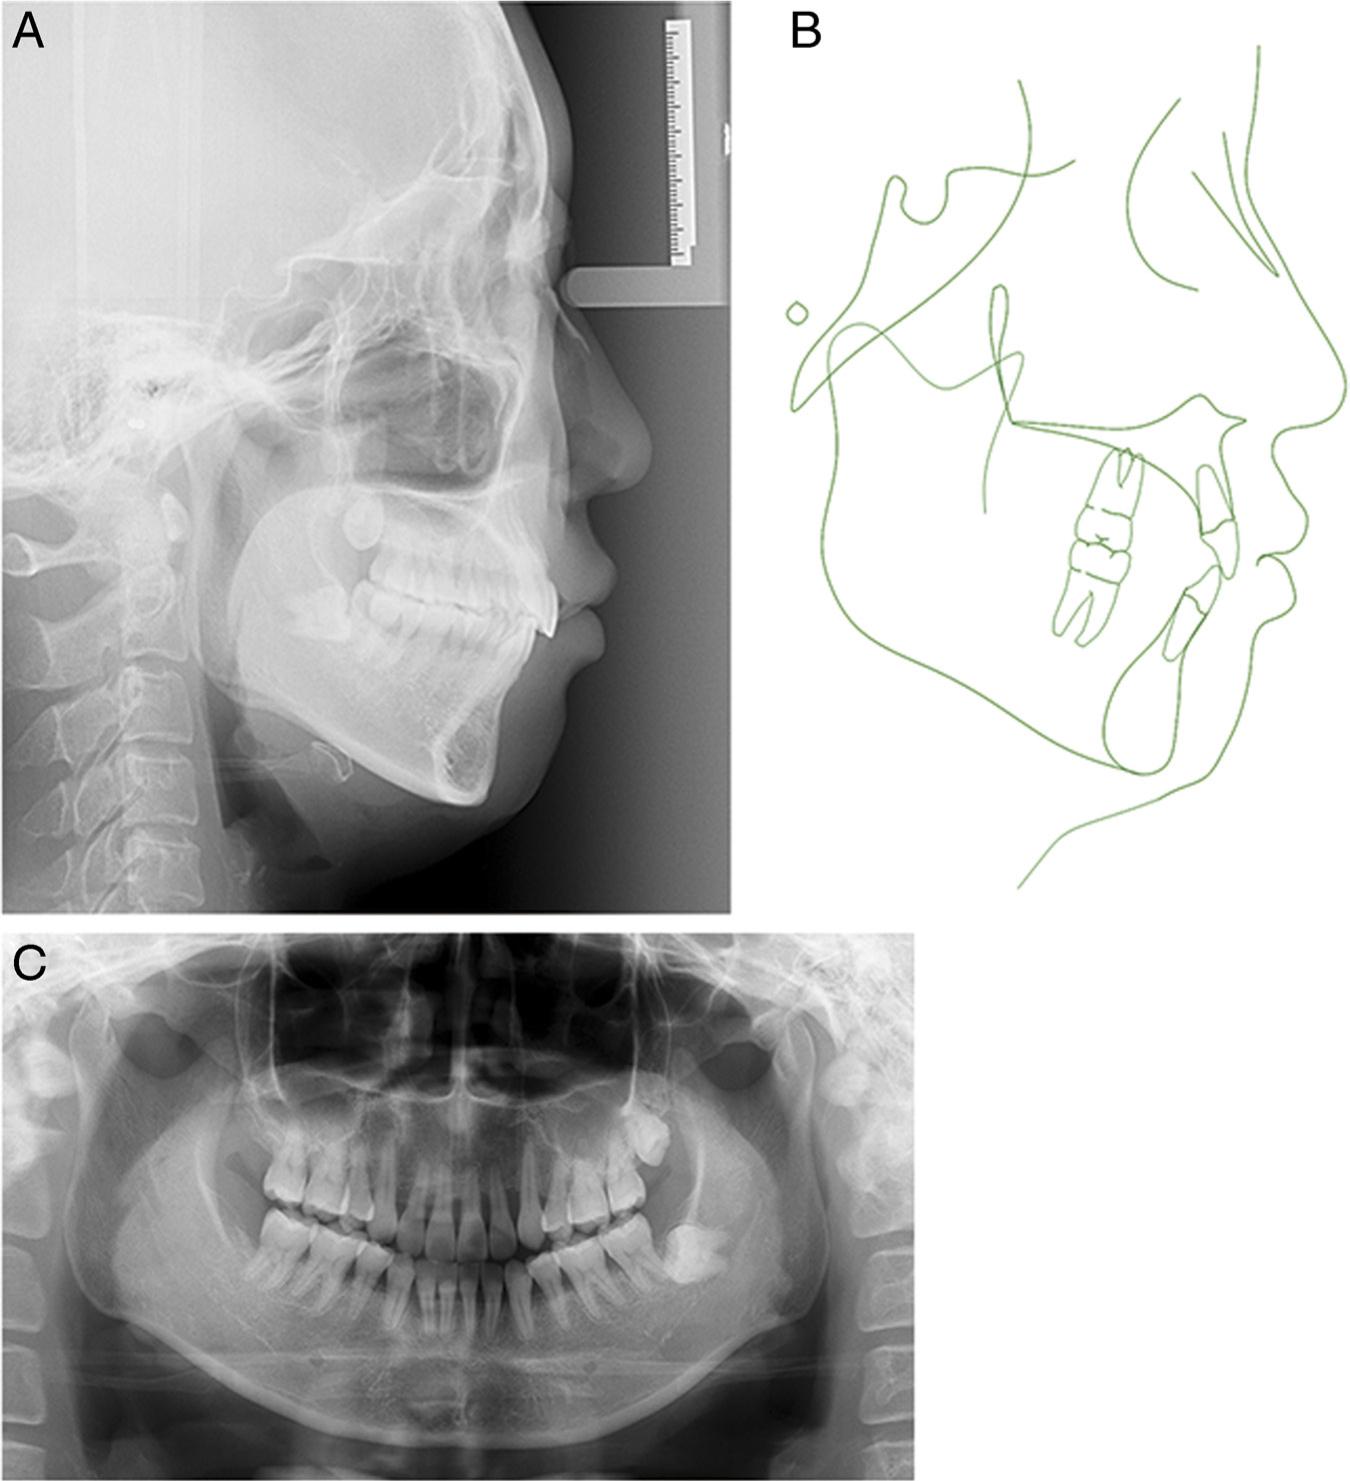

The panoramic radiographic findings revealed that the left mandibular third molar was horizontally impacted (Figure 3). A lateral cephalometric analysis showed a skeletal Class I pattern (ANB, 4.3°), a hyperdivergent growth pattern (FMA, 29.0°; GoGn-SN, 38.2°), and maxillary anterior tooth extrusion (PP-U1, 34.3 mm). The maxillary (U1-NA, 8.5 mm/32.2°) and mandibular incisors (L1-NB, 8.0 mm/31.0°; U1-L1, 118.1°) protruded. The soft tissue findings confirmed that the upper and lower lips were protrusive (the upper lip to E-line, 3.0 mm; lower lip to E-line, 7.0 mm) with an acute nasolabial angle (NLA, 77.0°) (Table I).

Figure 3.

Pretreatment radiographs and tracing: (A) lateral cephalometric radiograph; (B) cephalometric tracing; and (C) panoramic radiograph.